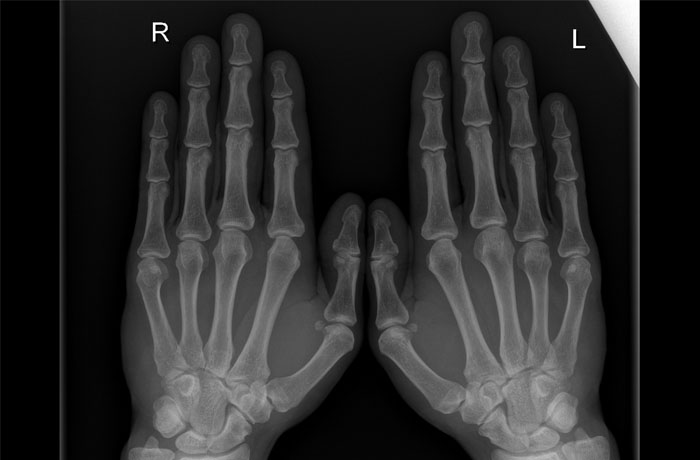

Контрактура Дюпюитрена – это рубцевание и укорочение соединительной ткани, покрывающей сухожилия мышц ладони (ладонного апоневроза). Процесс приводит к потере возможности разгибать пальцы. В большинстве случаев патологические изменения поражают безымянный палец и/или мизинец. В некоторых ситуациях страдают все пальцы одной или обеих рук.

На начальном этапе на ладонной поверхности у основания пальца возникает болезненное узловатое уплотнение. В большинстве случаев происходит рубцевание ограниченного участка апоневроза. При прогрессировании – на ладони прощупываются грубые тяжи, обеспечивающие «приведение» пальцев и невозможность их разгибания. Для человека становится трудным выполнение самых простых действий: умыться, причесаться, надеть перчатки, - становится проблемой.